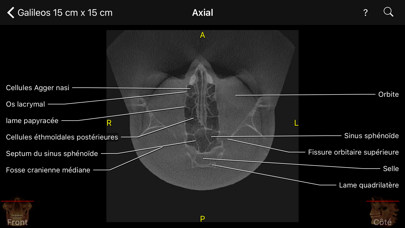

L’application CBCT permet aux cliniciens, résidents et étudiants en médecine dentaire d’apprendre les repères anatomiques de la même façon comme s’ils regardaient le volume via le logiciel de visualisation de données CBCT mais avec tous les repères visibles et animées sur toutes les vues MPR.

Le niveau d'interactivité et de visualisation est sans précédent. Cette application étonnante couvre des centaines de points de repère anatomiques visibles sur des volumes CBCT de petite à moyenne à grand champ de vue (FOV). Il vous permet également de tester vos connaissances à travers le mode test, ce qui est très "cool". Vous pouvez également rechercher un point d'intérêt ou le retrouver à partir d'une liste alphabétique et l'application vous l’indiquera.

- 3 ensembles de données de haute qualité de CBCT leaders de l'industrie, Carestream Dental et Sirona, en petit, moyen, et grand champ de vision (FOV).

- Plans de vue axial, frontal et sagittal.